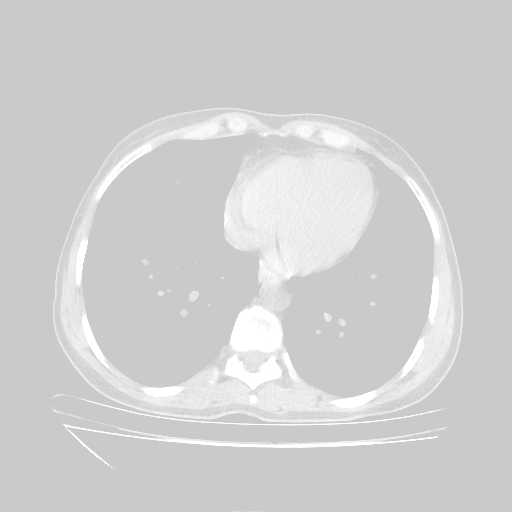

Slice 70 Targeting Evaluation

Slice: Slice_70

Conversion: NATIVE β†’ VENOUS

Image Grid

4Γ—3 grid: Rows show different image types (Original NATIVE, Reconstructed NATIVE, Original VENOUS, Generated VENOUS), Columns show windowing techniques (No Window, Lung Window, Mediastinum Window)

Original NATIVE CT scan (input)

No window - Raw intensity values